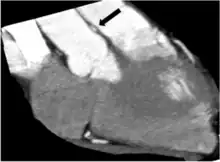

Cross-sectional computed tomography angiogram of RCA (between aorta and pulmonary artery) at the worst intramural site of compression (right anterior oblique projection). Black arrow = compressed intramural RCA.

Intravascular ultrasound imaging of intramural RCA during systole (left) and diastole (right) in a patient with mild symptoms.